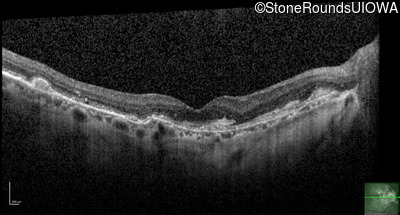

Optical Coherence Tomography - Left - 20/20 -2

Exemplar / OCT Stack

OCT Stack